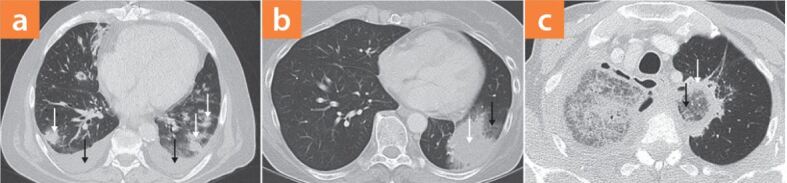

▶Abb. 6 zeigt typische pulmonale Veränderungen in der Computertomografie bei hämatologischen Patienten mit Schimmelpilzinfektionen. Bei Hochrisikopatienten mit pulmonalen Mykosen können singuläre, aber auch disseminierte, bilaterale Rundherde und Pleuraergüsse auftreten (▶Abb. 6a). Manchmal lässt sich eine von Milchglasinfiltraten umgebene Konsolidierung nachweisen, dieses Phänomen wird auch Halo-Zeichen (englisch: "halo sign") genannt (▶Abb. 6b). Pilze wie Aspergillus und Mucorales-Spezies wachsen angioinvasiv, die Milchglasinfiltrate des Halos entsprechen Hämorrhagien, die durch die in Blutgefäße einwachsenden Schimmelpilze entstehen. Im Rahmen dieser Angioinvasion kann es zu einem in der computertomografischen Angiografie sichtbaren Gefäßverschlusszeichen kommen (englisch: "vascular occlusion sign"), definiert als ein unterbrochenes Gefäß am Rand einer fokalen Läsion, ohne dass sich das Gefäß innerhalb oder peripher zur Läsion darstellen lässt. Zuweilen lässt sich noch ein weiteres Phänomen, das "umgedrehte" Halo-Zeichen (englisch: "reversed halo sign") beobachten (▶Abb. 6c). In diesem sind Milchglasinfiltrate von einer zirkulären Konsolidierung umgeben. Wobei mehr als zehn disseminierte Rundherde und Pleuraergüsse verdächtig auf das Vorliegen einer Mukormykose sind. Der Nachweis des "umgedrehten" Halo-Zeichens ist hochverdächtig auf das Vorliegen einer Mukormykose bei neutropenen, hämatopoetisch stammzell- oder solidorgantransplantierten Patienten. Das in diesem Patientenkollektiv auftrete Halo-Zeichen tritt zwar auch bei Mukormykosen auf, kommt jedoch öfter bei invasiven Aspergillosen vor [13].